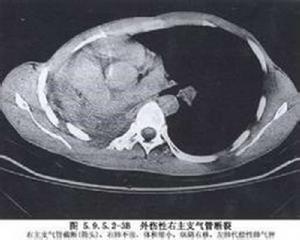

呼吸困難是氣管或支氣管破裂的突出症狀,引起呼吸困難的主要原因有:①氣管破裂引起的單側或雙側氣胸;②血液或分泌物阻塞下呼吸道;③並發肺挫傷;④受傷氣管或支氣管黏膜水腫或血腫等。嚴重的呼吸困難常伴有發紺。傷後早期常有咯血,咯血量多為少量至中量,罕有大量咯血者,有時為泡沫樣血痰。若支氣管破裂口與胸膜腔相通,可迅速發展為張力性氣胸。若縱隔胸膜尚完整,氣管或支氣管破口與胸膜腔不相交通,傷側肺仍有通氣,則氣胸表現不明顯。這類無氣胸表現的氣管或支氣管破裂大約為1/3,易被忽視而轉為慢性期。縱隔及皮下氣腫亦是氣管或支氣管破裂的常有症狀,常常起始於頸前胸骨切跡上方的皮下,並迅速向頸、胸及腹部蔓延,引起廣泛而嚴重的皮下氣腫。X線檢查早期可見脊柱前緣積氣透光帶,隨後積氣迅速增加出現嚴重的縱隔氣腫征。縱隔胸膜破裂者出現氣胸及液氣胸征。一側主支氣管斷裂時,立位胸片顯示傷側肺因失去支氣管的懸吊作用而墜落至胸腔底部心膈角處,而一般氣胸,萎陷的肺被壓向縱隔肺門部。這一X線表現稱之為“肺墜落征”,具有鑑別診斷價值。但支氣管周圍纖維膜未斷裂或存在血胸時,“肺墜落征”可不明顯。懷疑有支氣管損傷而傷情允許的情況下,可行急診纖維支氣管鏡檢查,對診斷及治療均有幫助。總之,對嚴重胸部閉合性損傷,若傷後很快出現呼吸困難、咯血、氣胸、縱隔及皮下氣腫,特別是經充分閉式引流及負壓吸引仍不能控制其張力性氣胸,就應考慮到氣管及支氣管破裂之可能。